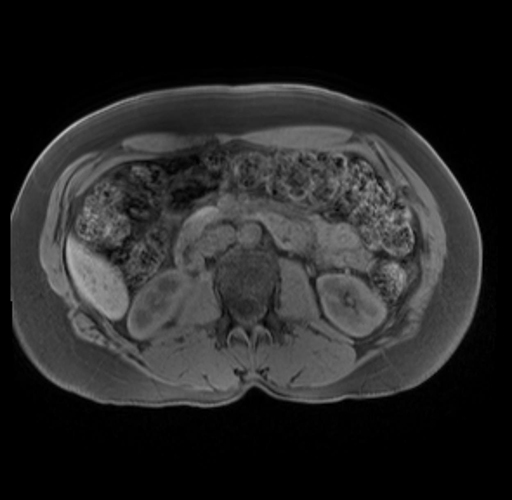

Imaging Analysis

Look through the patient's CT scan to identify any areas of concern for the necessary procedure.

Based on your CT findings, which issue(s) are present and would give reason for "planned slowing down moment(s)" in this case?

Considering a standard distal pancreatectomy procedure, what step(s) of the operation would you do differently in this case?